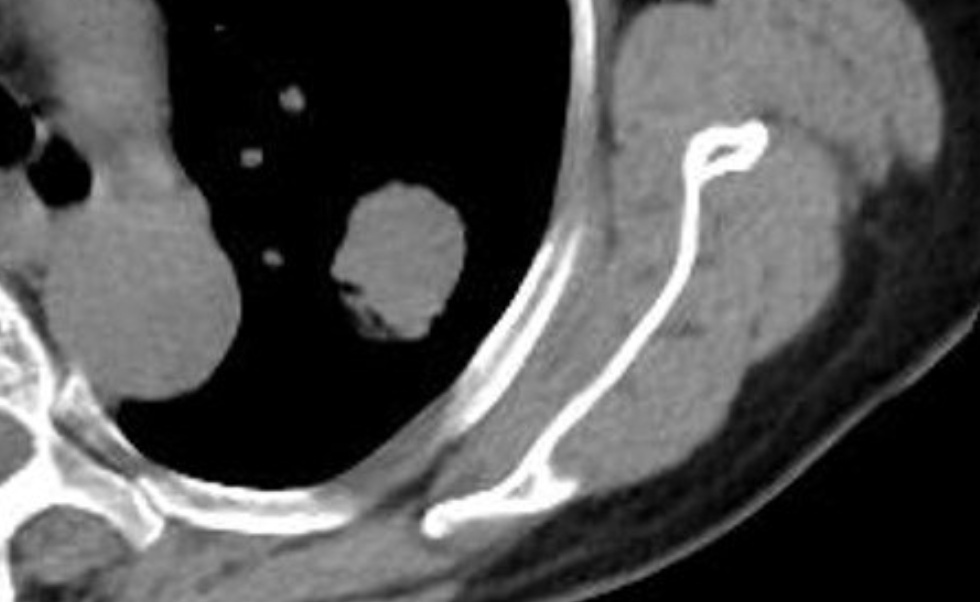

平扫CT肺窗

平扫CT纵隔窗密度约40HU

增强CT纵隔窗,肺结节密度增高至60HU,考虑恶性肿瘤

PET-CT显示病灶糖代谢摄取高,

诊断为恶性肿瘤